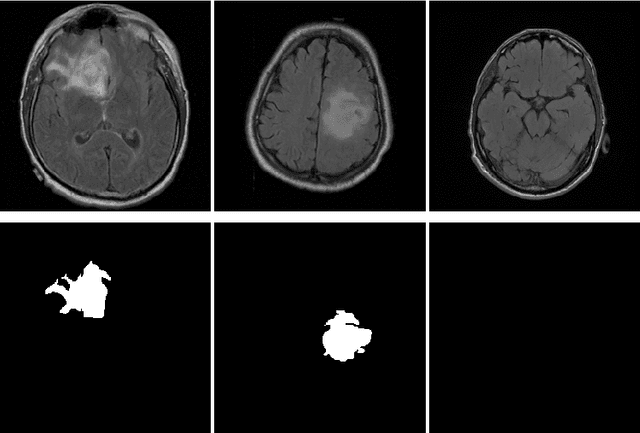

Abstract:In 2020, the SARS-CoV-2 virus causes a global pandemic of the new human coronavirus disease COVID-19. This pathogen primarily infects the respiratory system of the afflicted, usually resulting in pneumonia and in a severe case of acute respiratory distress syndrome. These disease developments result in the formation of different pathological structures in the lungs, similar to those observed in other viral pneumonias that can be detected by the use of chest X-rays. For this reason, the detection and analysis of the pulmonary regions, the main focus of affection of COVID-19, becomes a crucial part of both clinical and automatic diagnosis processes. Due to the overload of the health services, portable X-ray devices are widely used, representing an alternative to fixed devices to reduce the risk of cross-contamination. However, these devices entail different complications as the image quality that, together with the subjectivity of the clinician, make the diagnostic process more difficult. In this work, we developed a novel fully automatic methodology specially designed for the identification of these lung regions in X-ray images of low quality as those from portable devices. To do so, we took advantage of a large dataset from magnetic resonance imaging of a similar pathology and performed two stages of transfer learning to obtain a robust methodology with a low number of images from portable X-ray devices. This way, our methodology obtained a satisfactory accuracy of $0.9761 \pm 0.0100$ for patients with COVID-19, $0.9801 \pm 0.0104$ for normal patients and $0.9769 \pm 0.0111$ for patients with pulmonary diseases with similar characteristics as COVID-19 (such as pneumonia) but not genuine COVID-19.